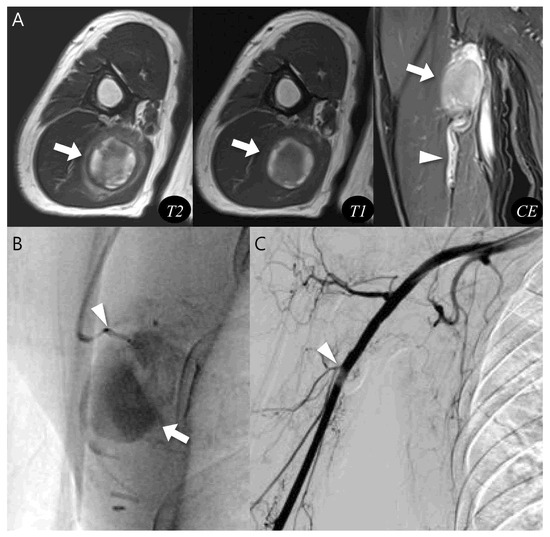

Second, the following MRI features were assessed—including lesion morphology, internal characteristics, pulsatile artifact, and relationship to adjacent structures (Figure 1). Morphology was categorized as either ovoid or multilobular in contour. Internal characteristics related to hematoma were evaluated as follows: (1) outermost peripheral low SI on T1WI—indicating a fibrous pseudocapsule with hemosiderin or collagenous tissue [22,23]; (2) inner peripheral high SI on T1WI, located just inside the low-signal rim—reflecting mural thrombus with methemoglobin [11]; (3) central high SI on T1WI—consistent with subacute/mature methemoglobin or repetitive rebleeding deposits [24]; (4) central flow void on T1WI and T2WI, appearing as a distinct signal void or markedly hypointense core due to rapid intraluminal blood flow, observed on all sequences (but most conspicuous on T2WI due to strong flow-related dephasing)—indicative of fast-flow blood [25,26]; (5) septation—representing internal fibrous septa or loculations [5]; and (6) nodular enhancement—suggesting granulation tissue or neovascularization.

Figure 1.

MRI findings of pseudoaneurysm (A–C) and chronic expanding hematoma (D–F). (A) Axial T2-weighted and (B) T1-weighted images show an intramuscular, ovoid mass with a central flow void (asterisk in (A,B), fast-flow blood), pulsatile artifact (dotted arrow in (A,B) and inner peripheral high SI on T1-weighted image (arrows in (B), mural thrombus). (C) Coronal T2-weighted image demonstrates neurovascular involvement (arrowhead). (D) Axial T2-weighted and (E) T1-weighted images reveal a multilobular subcutaneous mass with heterogeneous signal intensity with septations (arrow in (D,E)). (F) Coronal T1-weighted contrast-enhanced image demonstrates nodular enhancement (arrowheads, granulation tissue) within the mass.

A pulsatile artifact (Figure 1) was defined as a motion-related imaging artifact on MRI that arises from the periodic pulsation of blood flow, typically appearing as ghosting of SI along the phase-encoding direction and was considered as an indirect marker of active vascular flow [27,28].

Last, neurovascular bundle involvement (Figure 1) was considered positive when displacement, encasement or infiltration of adjacent neurovascular structures was observed [29].